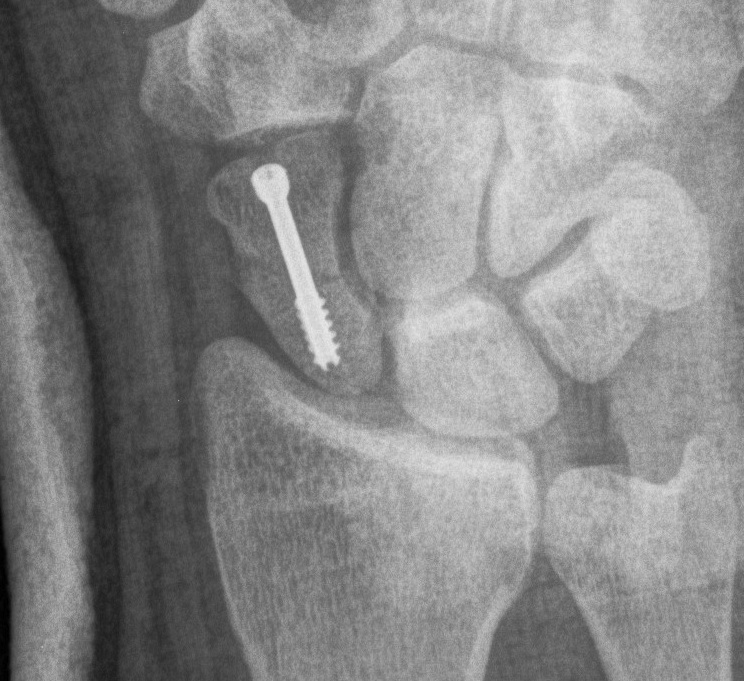

Scaphoid waist fracture 1 mm displaced

Scaphoid fracture with significant displacement

Scaphoid proximal pole fracture